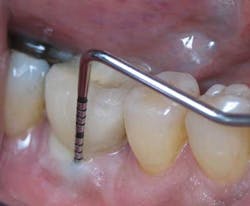

Fig. 2: Clinical probing showing suppuration around the implant-supported crown.

Fig. 4: Probing around implant-supported crown reveals depth and suppuration.